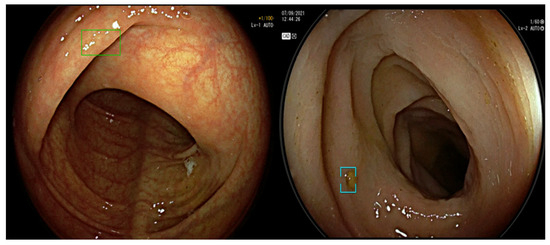

3.1. Artificial Intelligence-Assisted Detection (CADe)